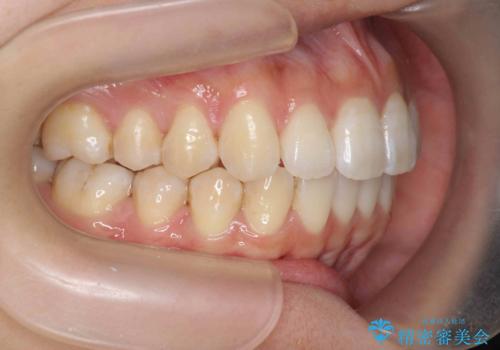

- 前歯の噛み合わせの開きの改善を求めて来院されました。

奥歯はほとんど動かさず(奥歯の噛み合わせはほとんど変えず)前歯のIPR矯正でガタつき前突感(出っ歯感)の改善を計画します。

ほとんど前歯のみの矯正治療であることからトータル14枚のマウスピースで並べるインビザラインライトによる治療を行います。